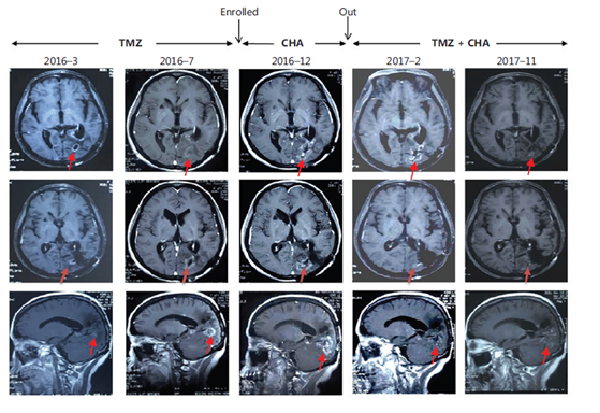

治療惡性腦膠質瘤Ⅰ期臨床研究特殊病例分析:注射用綠原酸有效延長受試者生存期,并能一定程度解除受試者對替莫唑胺的耐藥現象

受試者入組時替莫唑胺耐藥且疾病進展;

使用注射用綠原酸后病情得到有效控制,出組后再次使用替莫唑胺治療,MRI結果顯示替莫唑胺再次起效。

患者采用替莫唑胺與注射用綠原酸交替使用、聯合治療的方案,顱內病灶目前已完全消失,從確診至今,生存期已超過13年。

病例圖片來源 Kang, Z. , Li, S. , Kang, X. , Deng, J. , Yang, H. , & Cheni, F. , et al. (2023). Phase Ⅰ study of chlorogenic acid injection for recurrent high-grade glioma with long-term follow-up. 癌癥生物學與醫學:英文版, 20(6), 465-476.